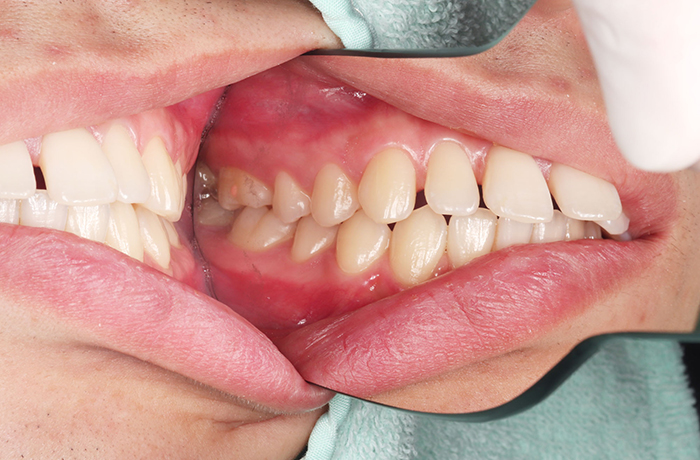

A様

治療前

年齢 31歳

性別 女性

治療名称 マウスピース型カスタムメイド矯正歯科装置(インビザライン)・コンプリヘンシブパッケージ(難症例)

総額治療費用 935,000円(税込10%) 金額備考 精密検査料・診断料 33,000円(税込10%)

治療期間 3年4か月 通院頻度など 1か月ごと(途中から3~4か月ごと)

患者の症状 叢生、正中のずれ、上顎左右側切歯の口蓋側転位(交叉咬合)

治療方法 非抜歯で、マウスピース型カスタムメイド矯正歯科装置(インビザライン)による矯正

歯列弓を拡大することで非抜歯を可能にしました。

治療結果 側切歯の交叉咬合は解消、上下正中のずれも改善し咬み合わせが良くなりました。